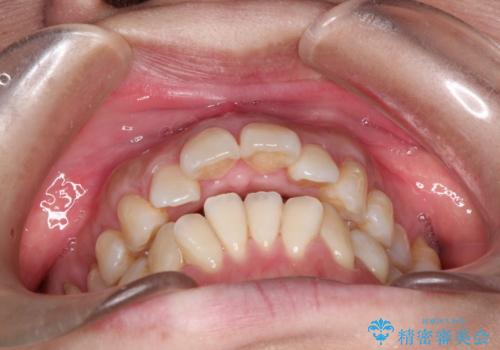

- 出っ歯がきになるとのことで来院されました。

上顎の前歯は前方に傾斜しており、下あごの前歯にもガタガタがありました。